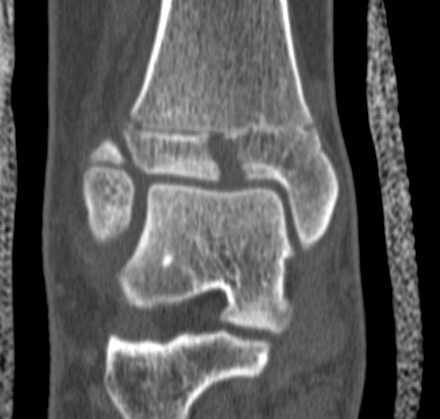

CT

Type III on coronal

Type II on sagittal

3 point star on axial

Triplanar Fracture

Definition

- fracture in coronal, sagittal and transverse planes

- 2, 3 or 4 part

Varieties

2 part

- can be medial or lateral based of site of main distal fragment

- typically anterolateral epiphysis attached to posterior metaphysis

- anteromedial intact distal tibia

3 part

- additional separate anterolateral epiphysis / Tillaux

4 part

- additional separate metaphyseal fragment